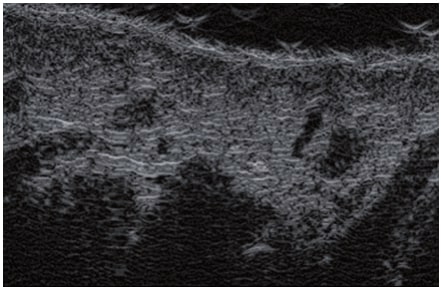

Die Doppler-Sonographie ermöglicht die Darstellung großer Gefäße und Perforatoren, die sich meist in tieferen Bereichen des subkutanen Gewebes befinden. Mit klassischem Ultraschall lassen sich kleinere Gefäße jedoch nicht darstellen. Für die Darstellung kleinerer Gefäße, die oberflächlich unter der Epidermis und im oberen subkutanen Gewebe liegen, wird HFU eingesetzt. Mit Sonden über 20 MHz Frequenz erhält man hochauflösende Ultraschallbilder, auf denen Objekte kleiner als 0,1 mm unterscheidbar sind. Mit zunehmender Auflösung nimmt jedoch die Eindringtiefe ab. Je nach Sonde und Gerät beträgt die maximale Eindringtiefe etwa 20–30 mm. Diese Eindringtiefe bei gleichzeitig hoher Bildauflösung ermöglicht die Beurteilung sehr kleiner Gefäße. HFU erlaubt die genaue Bestimmung des Verlaufs und der Lage kleiner Gefäße in der Haut, was entscheidend für die Wahl der Verschlussmethode und die Planung des Eingriffs ist. Oft sind an der Hautoberfläche nur wenige Gefäße sichtbar – erst durch die Ultraschalluntersuchung lässt sich die tatsächliche Anzahl und der Verlauf feststellen. Für einen erfolgreichen Verschluss muss das gesamte Gefäß behandelt werden, nicht nur der sichtbare Teil, da sonst eine schnelle Rekanalisation erfolgt (7). Häufig ändert das an der Haut sichtbare Gefäß seinen Verlauf, wird gewundener und zieht in tiefere Hautschichten (8). HFU ermöglicht zudem die Darstellung der Perforatoren zwischen kleinen Gefäßen und die Messung grundlegender Parameter wie Durchmesser, Wandstärke, Tiefe und Blutfluss (6). Mit der 40-MHz-Sonde von Ultrasonix kann auch der Blutfluss mittels Farbdoppler visualisiert werden.